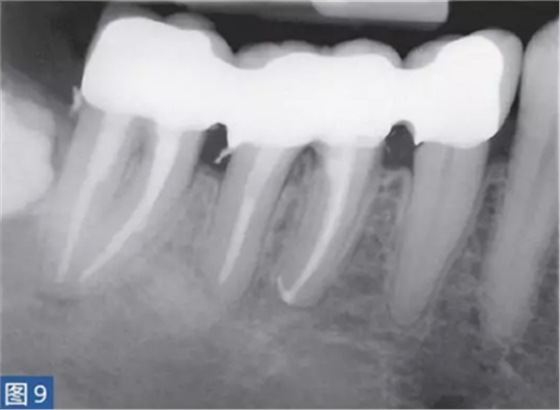

急性根尖周膿腫(AAA acute apical abscess)

急性根尖膿腫(圖8 和9)是一種局部的或者彌漫性的液性病變。由壞死牙髓產(chǎn)生的微生物和非微生物刺激所引起的嚴(yán)重炎癥反應(yīng)造成了根尖周組織的破壞。患者通常表現(xiàn)出中度至重度疼痛,根據(jù)嚴(yán)重程度還可能出現(xiàn)發(fā)熱和白細(xì)胞增多的全身癥狀。

臨床診斷顯示牙髓電活力測(cè)試結(jié)果陰性。叩診和觸診通常會(huì)引起疼痛。如果膿腫僅限于骨內(nèi),則不出現(xiàn)腫脹癥狀。放射學(xué)檢查,根尖周組織表現(xiàn)從無變化到發(fā)生明顯變化。

圖9:47 牙齒AAA。根管治療后。患者在其家庭牙醫(yī)處做臨時(shí)義齒修復(fù)12 個(gè)月后的檢查。